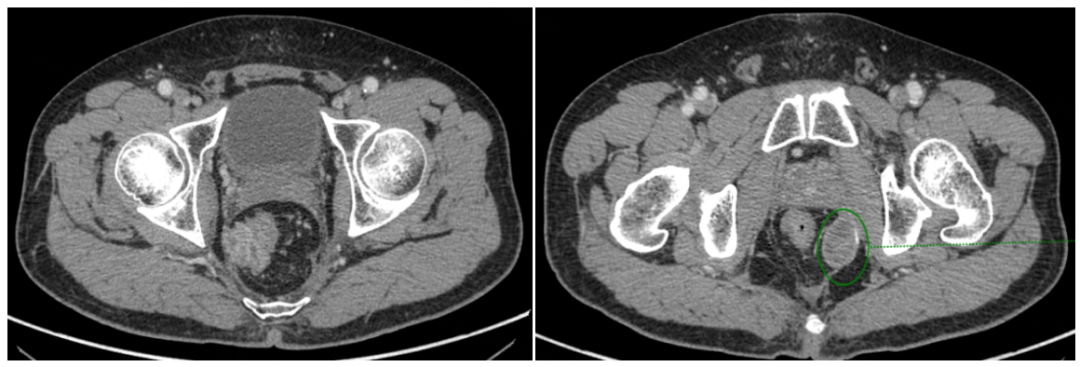

2020年4月10日至2020年10月10日,给予二线第1-10周期FOLFIRI方案化疗联合贝伐珠单抗靶向治疗,2020年6月26日,9月7日,两次疗效评估为SD。

2020年11月20日,再次腹盆腔CT增强:“直肠癌术后+前腹壁造瘘术”后改变,局段直肠壁增厚伴邻近筋膜增厚、腹膜反折处结节样增厚,需考虑肿瘤复发可能,较前片(2020年9月7日)略有进展,较前片(2020年4月10日)明显进展。疗效评估为疾病进展(PD)。